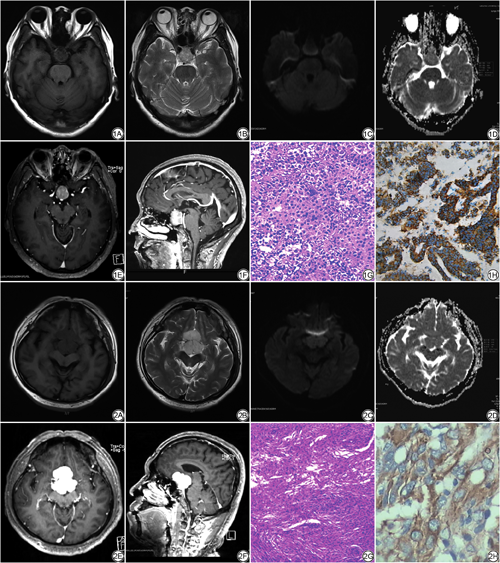

42例垂体大腺瘤中,T1WI呈低信号,T2WI呈中等偏高信号。5例瘤内发生坏死囊变,囊变部分T1W1呈低信号,T2WI呈高信号;4例瘤内出血,TIWl及T2WI均呈不均匀高信号;增强扫描轻中度强化28例,瘤内出血坏死囊变时不均匀强化;本组中90%的肿瘤较大,突破鞍隔向上生长,压迫视交叉,使垂体柄受压移位,甚至显示不清,且包绕两侧颈内动脉和海绵窦40例,形成较典型的“束腰征”39例(图1)。40例鞍区脑膜瘤中,肿瘤实性部分未见明显出血,T1WI显示较低信号,T2WI呈中等或稍高信号,增强后肿瘤明显均匀强化38例,邻近脑膜明显增厚并强化25例,即“脑膜尾征”(图2)。其影像征象如表1所示。

在42例垂体大腺瘤中,肿瘤实体成分在DWI上19例呈高或稍高信号,15例呈等信号,8例呈低信号;ADCmax、ADCmean和ADCmin分别为(1.126±0.266)×10-3 mm2/s、(1.052±0.271)×10-3 mm2/s和(0.971± 0.288)×10-3 mm2/s。在40例鞍区脑膜瘤中,肿瘤实体成分在DWI上22例呈高或稍高信号,15例呈等信号,3例呈低信号。两组肿瘤DWI信号强度比较无统计学意义(P>0.05) (表1);ADCmax、ADCmean和ADCmin分别为(0.855±0.176)×10-3 mm2/s、(0.817±0.177)×10-3 mm2/s和(0.777±0.182)×10-3 mm2/s,均小于垂体大腺瘤。两组肿瘤实性成分ADCmax值、ADCmin值、ADCmean值比较差异具有统计学意义(P<0.001) (表2;图3)。

DWI通过反映组织间水分子弥散情况,提供肿瘤内部微环境信息[19, 20]。本研究中,MRI基本征象结合ADC值诊断垂体大腺瘤和鞍区脑膜瘤的准确率明显高于MRI基本征象(表3),ADC值在两种肿瘤鉴别中有明显统计学意义,而DWI信号在二者间无统计学意义,这可能是由于DWI 信号的影响因素比较多,主要有扩散敏感系数(b)、ADC值、T2穿透效应、各向异性等[21];影响肿瘤ADC值的因素相对较少,包括肿瘤细胞密度、核浆比、肿瘤基质及胞浆内大分子物质含量等。当肿瘤细胞排列紧密、核浆比例高、基质稀少时,水分子扩散受限,DWI信号增高,ADC值较低[22, 23]。本研究中鞍区脑膜瘤的ADCmax、ADCmean和ADCmin值均低于垂体大腺瘤(P<0.001),ADCmax对鉴别垂体大腺瘤和鞍区脑膜瘤的能力相对高于ADCmin和ADCmean,AUC值为0.877 (最佳截断值为0.970×10-3 mm2/s),这些发现与先前的研究结果一致[24],分析其原因可能与细胞类型和核浆比不同有关。垂体大腺瘤内纤维组织增生,疏松排列;而脑膜瘤细胞彼此之间紧密连接,细胞间区域被大量的胞浆与细胞内复杂蛋白分子紧密相连[25],限制了细胞内外水分子的运动。因此,与垂体大腺瘤相比,鞍区脑膜瘤细胞排列紧密,细胞外间隙减小,基质稀少,从而限制了水的扩散。这种组织学差异解释了ADC图上的差异。